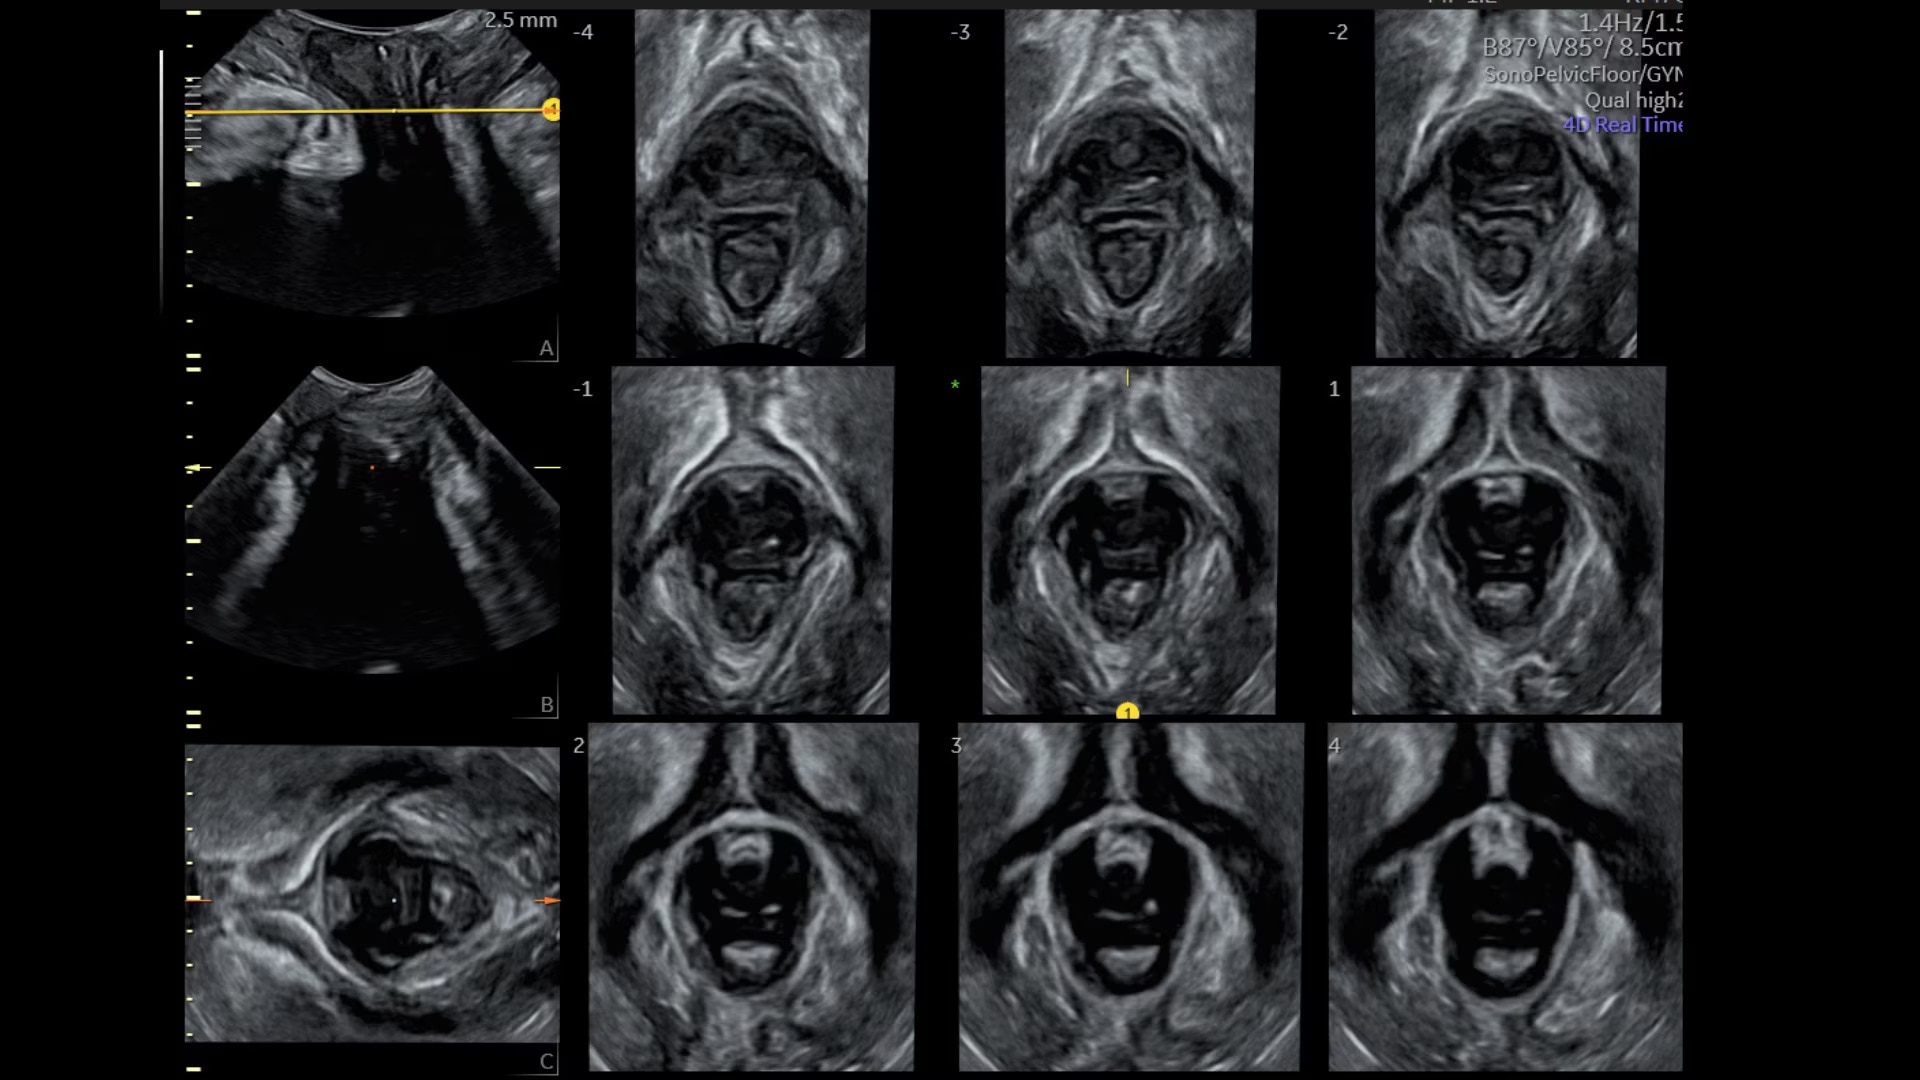

Sonopelvicfloor

Assess pelvic floor anatomy using guided workflow & AI

Using a guided workflow and AI, SonoPelvicFloor:

• removed exam complexity by automating plane alignment and measurements

• can reduce keystrokes by up to 75% and offer users a time savings of up to 80%